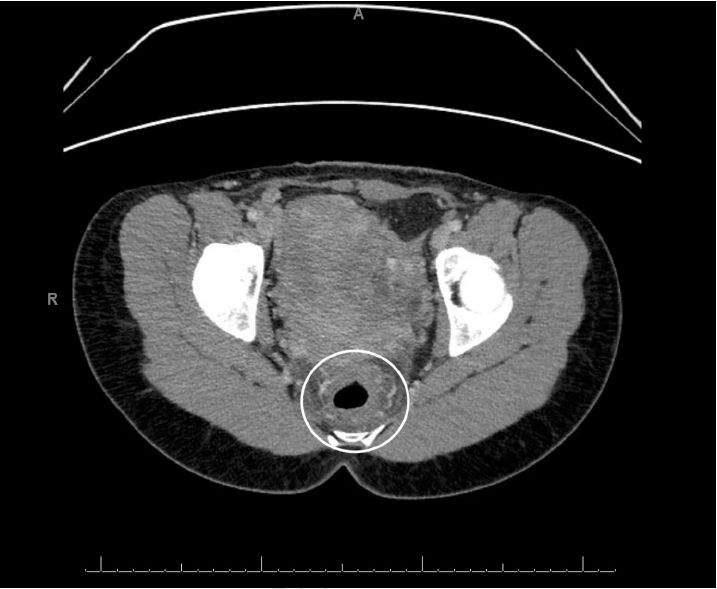

HIV和粪便检查结果为阴性。腹部和骨盆的计算机断层扫描(CT)扫描提示了异常发现(图A,图B),因此,我们又用内窥镜对患者进行了检查。在接下来的几天,乙状结肠镜检查的结果如图C、图D和图E。

图A

腹部和骨盆的CT显示直肠壁增厚,提示直肠的炎症和充血,即直肠炎(图A,B)。乙状结肠镜检查的结果显示直肠和远端乙状结肠内的粘膜严重充血,伴随弥漫性红点(图C,D)与表面渗出物,且直肠和乙状结肠远端的粘膜脆弱。这些发现与化学直肠炎,特别是过氧化氢诱导的化学直肠炎的表现一致。